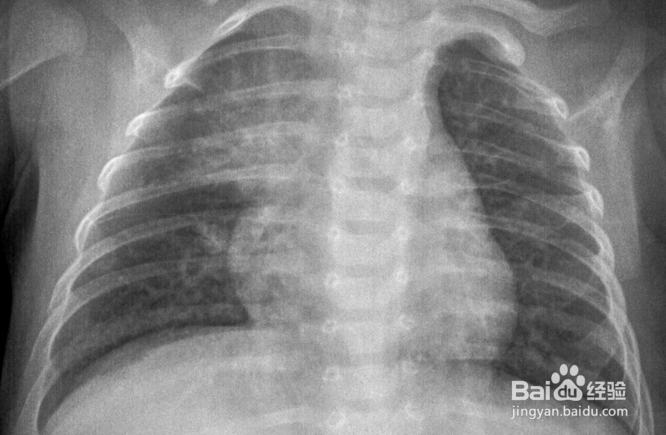

4、呼吸道感冒

新生儿肺炎等疾病会导致宝宝的发烧,而且一般伴有咳嗽和哭闹,这种情况一定要及时就医。